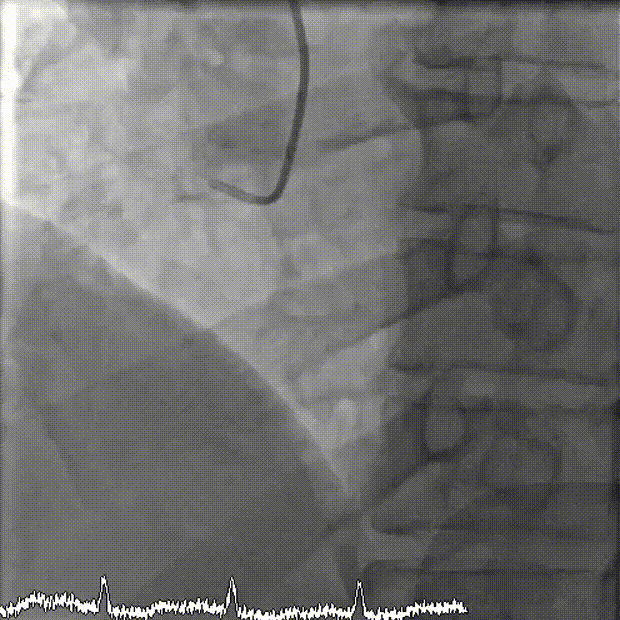

抽吸【例】量|【兑】话血栓抽吸